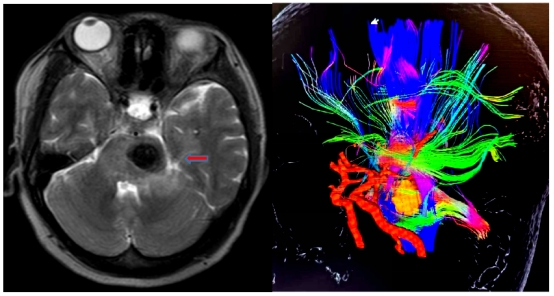

图1.术前核磁显示脑干病变位置(箭头所示)及周围密集的神经纤维及血管

脑干是生命中枢,控制人体的呼吸和心跳等重要活动,其内密集存在和人体运动、感觉相关的神经纤维,而且位置深在,曾经被认为是手术禁区,但是不立即手术治疗,患者就会丧失基本的肢体功能,甚至失去生命。